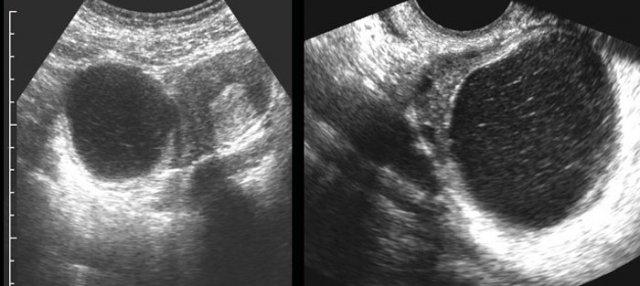

Ca lâm sàng 5

Các nang xuất huyết tồn lưu thường chứa các khối đặc, không có mạch máu, không đồng nhất, đại diện cho cục máu đông.

Sự co rút của các cục máu đông này thường tạo ra các bờ lõm (đầu mũi tên).